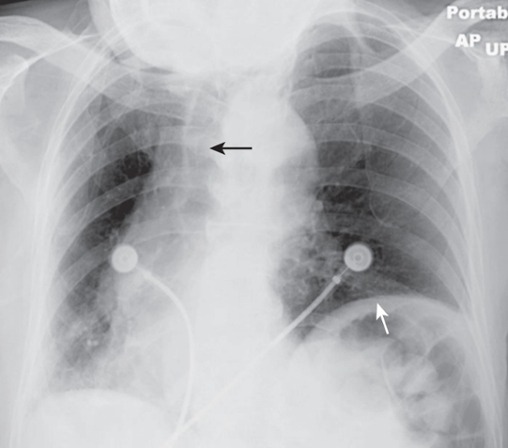

Endotracheal Tube (ETT)

A tube placed in the trachea to ensure an open airway, visible on X-ray.

Central Venous Catheter (CVC)

A catheter placed in a large vein that can be viewed on radiographs for positioning verification.

Pulmonary Artery Catheter

A type of catheter used to monitor heart function, which should not be kinked or malpositioned as seen on X-ray.

Airspace Disease (pneumonia)

Frontal and lateral views of the chest demonstrate airspace disease on the lateral film (B) in the right lower lobe (white arrow) that may not be immediately apparent on the frontal film (you can see the pneumonia in the right lower lobe in [A] [black arrow]).

In this case, a right lower lobe pneumonia superimposed on the lower spine on the lateral view makes the spine appear “whiter” (more dense) just above the diaphragm. This is called the spine sign.